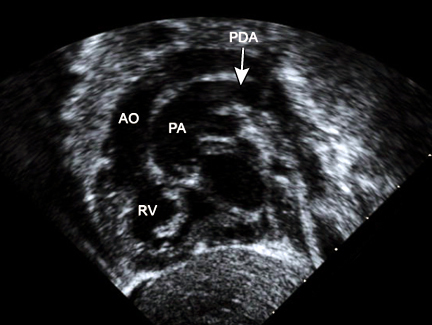

Neonate presents with late cyanosis. You hear a “machine like murmur” on auscultation.

Pathogenesis of this disease?

Patent ductus arteriosus.

Fetal period, shunt is from right to left (normal) to bypass lung circulation.

In neonatal period, lung resistance decreases, shunt becomes left to right, RVH and/or LVH and heart failure occurs.

What can you use to close a PDA?

What could you use to maintain patency? When would you want to do that?

Endomethacin (indomethacin) ends patency of PDA

PGE kEEps it open - use to sustain life in conditions such as transposition of the great vessels.

(Low O2 tension also keeps PDA open)